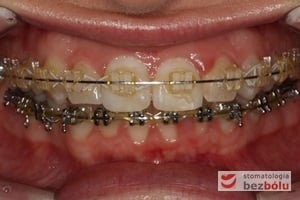

Leczenie bezekstrakcyjne z wykorzystaniem strippingu

Pacjentka lat 22 zgłosiła się do naszej placówki celem podjęcia leczenia ortodontycznego. Głównym oczekiwaniem pacjentki była poprawa estetyki uśmiechu oraz brak ekstrakcji zębów na drodze do jej uzyskania. Ze względu na liczne stłoczenia zębów w górnym i dolnym łuku, dość duży materiał zębowy w porównaniu z bazą kostną, a także zgryz przewieszony boczny prawostronny po dokładnej analizie cefalometrycznej oraz analizie modeli diagnostycznych zastosowano leczenie bezekstrakcyjne z wykorzystaniem strippingu jako alternatywy dla usuwania zębów, mającego na celu uzyskanie miejsca w łuku na uszeregowanie zębów. Po fazie aktywnego leczenia trwającego 18 miesięcy zastosowano leczenie retencyjne w postaci szyny retencyjnej w łuku górnym oraz retainera stałego w łuku zębowym dolnym klejonego od kła do kła.